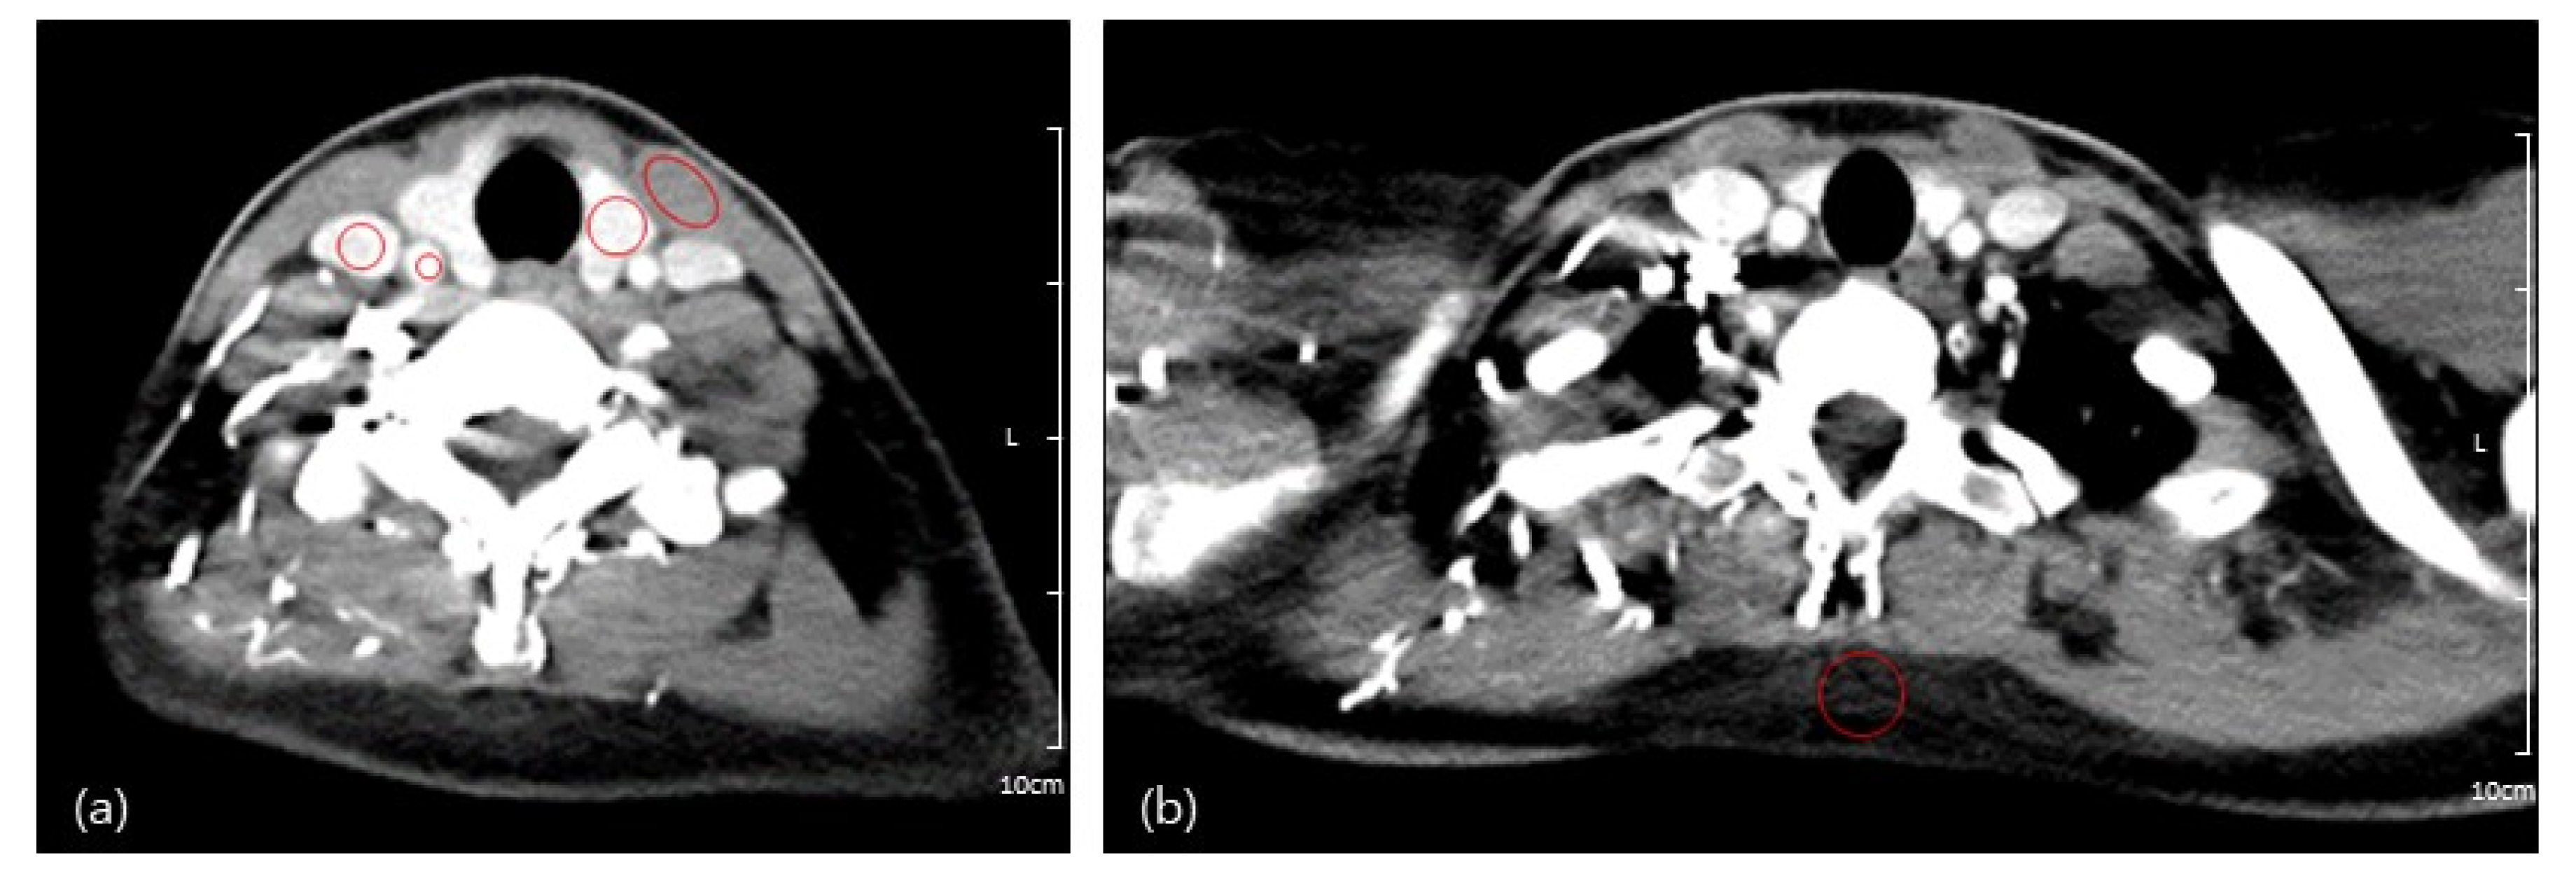

Quantitative image analysis was performed by two trained researchers using the PACS system in our institution. They identified five regions of interest (ROIs) to assess the Hounsfield unit (HU) and SD of the thyroid gland, sternocleidomastoid muscle (SCM), internal jugular vein (IJV), common carotid artery (CCA), and subcutaneous fat of the posterior neck with circular ROIs manually drawn as large as possible (Figure 2). These measurements were reviewed by one radiologist for appropriateness.

Figure 2.

(a) Quantitative analysis of CT images on which two trained researchers drew five regions of interest in the thyroid gland, sternocleidomastoid muscle (SCM), internal jugular vein (IJV), common carotid artery (CCA); and (b) subcutaneous fat of the posterior neck.